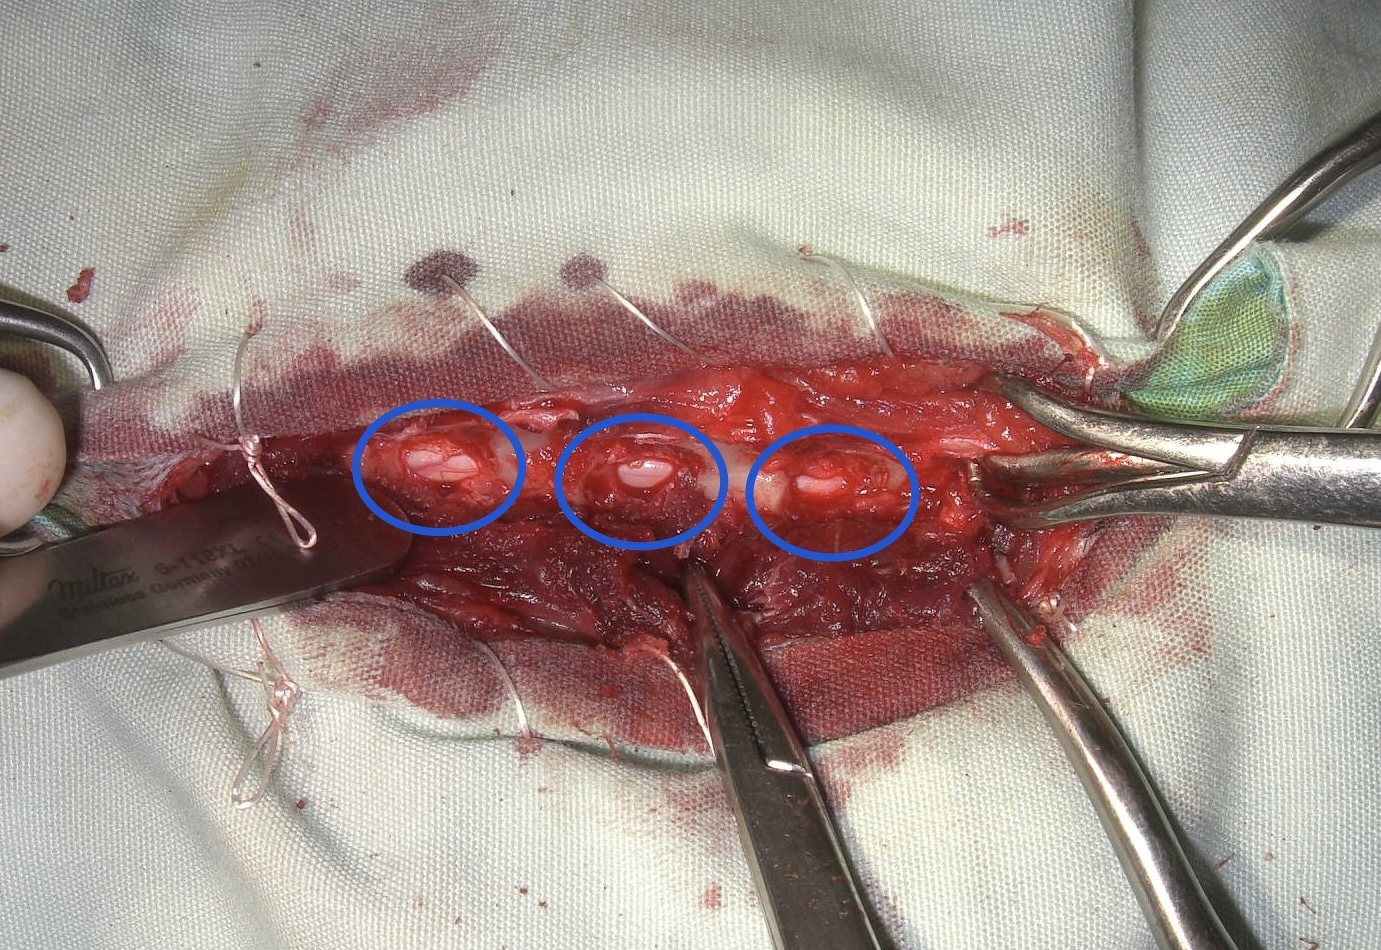

この写真は、椎間板ヘルニアの手術の写真です。この子は急な後肢麻痺を主訴で来院し、最初消炎剤を中心とする内科治療を行いましたが反応せず、脊髄にかかった圧力を減圧する目的の片側椎弓切除術(ヘミラミネクトミー)を実施しました。脊髄造影の結果、椎間板物質により腰の部分の脊髄が圧迫されていることがわかりました。脊髄を圧迫していた逸脱した椎間板物質を除去するために、背骨に小さな穴(青い丸の部分)を受傷部位の前後合わせて三つ開けて、脊髄の減圧を図っています。幸いこの子は歩行可能な状態まで回復することができました。